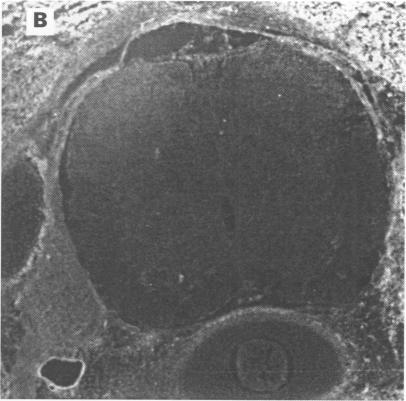

Of 45 patients with PNS whose serum was probed on paraformaldehyde fixed rat brain sections, 11 patients were identified whose serum samples recognised a cytoplasmic antigen in a subpopulation of glial cells in the white matter of adult rat brainstem, cerebellum, and spinal cord that were double labelled with a monoclonal antibody specific for oligodendrocytes. All serum samples reacted with a 66 kDa protein of newborn rat brain on western blot analysis. These antibodies were designated as anti-CV2 antibodies. Only one of the 11 patients had one of the well characterised autoantibodies (anti-Hu). Five patients had cerebellar degeneration, three had limbic encephalitis, two had encephalomyelitis, and one had Lambert-Eaton myasthenic syndrome. The tumours were small cell lung cancer or undifferentiated mediastinal cancer in seven patients, uterine sarcoma in two, and malignant thymoma in two. Among 1061 control serum samples, only two patients had anti-CV2 antibodies. One had small cell lung cancer and the other malignant thymoma.

在45例PNS患者中,用其血清检测经多聚甲醛固定的大鼠脑切片,发现11例患者的血清样本能识别成年大鼠脑干、小脑和脊髓白质中胶质细胞亚群的一种胞质抗原,这些胶质细胞用少突胶质细胞特异性单克隆抗体进行了双重标记。所有血清样本在蛋白质印迹分析中均与新生大鼠脑的一种66 kDa蛋白发生反应。这些抗体被命名为抗CV2抗体。11例患者中只有1例具有一种已明确的自身抗体(抗Hu)。5例患者有小脑变性,3例有边缘叶脑炎,2例有脑脊髓炎,1例有兰伯特-伊顿肌无力综合征。肿瘤在7例患者中为小细胞肺癌或未分化纵隔癌,2例为子宫肉瘤,2例为恶性胸腺瘤。在1061份对照血清样本中,只有2例患者有抗CV2抗体。1例患有小细胞肺癌,另1例患有恶性胸腺瘤。